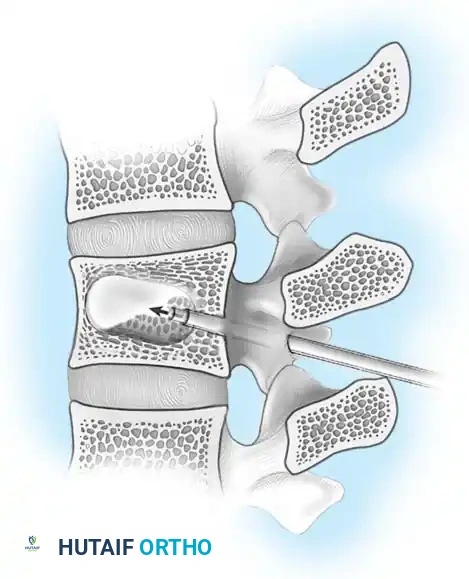

Compression of neural elements by retropulsed bone fragments can be addressed via two primary modalities:

- Indirect Decompression (Ligamentotaxis): Utilizes posterior distraction instrumentation and an intact PLL to pull retropulsed fragments out of the spinal canal. This is highly effective if performed acutely (< 72 hours). However, if surgery is delayed, fracture consolidation renders indirect reduction ineffective.

- Direct Decompression: Achieved via an anterior corpectomy or a posterolateral approach (e.g., transpedicular or costotransversectomy). This is mandatory for severely comminuted fractures where multiple bone fragments have breached the canal and cannot be reduced by ligamentotaxis alone.